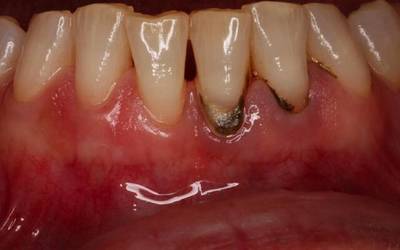

Фото 3. Абсцедирующий пародонтит. В области коренных зубов наблюдается гнойный абсцесс и сильная припухлость.

Симптомы заболевания: кровоточивость десен, углубление пародонтального кармана до четырех миллиметров, подвижность зубов, возникновение болевых ощущений даже в состоянии покоя, появление гнойных мешочков.

Причины возникновения заболевания — зубной налет и камень, а также запущенный гингивит и другие патологии функционирования организма.

Чаще всего пораженный зуб удаляют, но в некоторых ситуациях возможно лечение без операции.